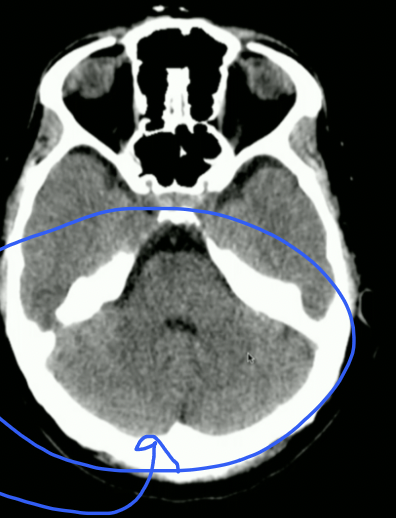

<p>What fossa?</p>

What fossa?

• Posterior Cranial Fossa

• THAT IS CEREBELLUM not Occipital Lobe

<p>What Part of Brain Stem?</p>

What Part of Brain Stem?

• Pons

• Look for Basilar Groove

<p>What Part of Brainstem?</p>

What Part of Brainstem?

• Medulla Oblungata

• Stops at Foramen Magnum